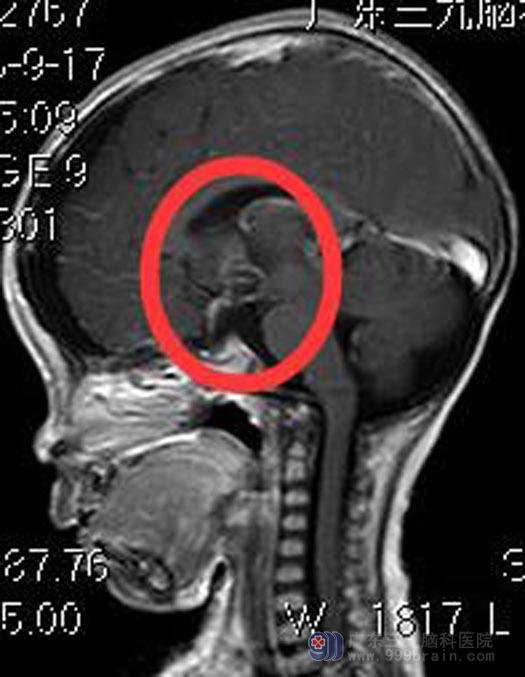

来到广东三九脑科医院时,琪琪的精神状态非常差,急诊行头颅MR检查,提示:鞍区(鞍上为主)示一团块状囊实性占位性病变,大小约3.5cm×3.3cm ×4.3cm,考虑颅咽管瘤,幕上梗阻性脑积水(中度),低钠血症。看着奄奄一息的孩子,父母欣然接受手术治疗。

综合神经外科鲁明主任主刀,在全麻下行鞍区颅咽管瘤切除术,术中显微镜下见肿瘤位于鞍区,呈灰白色(其间夹带部分淡黄色成分),质软,血供较丰富,显微镜下分块切除,肿瘤起源于垂体柄,肿瘤全切,下丘脑、垂体柄及重要血管保留完整,手术顺利。没有出现尿崩、离子紊乱等术后并发症,康复出院。术后病理结果提示:颅咽管瘤。

▲手术前